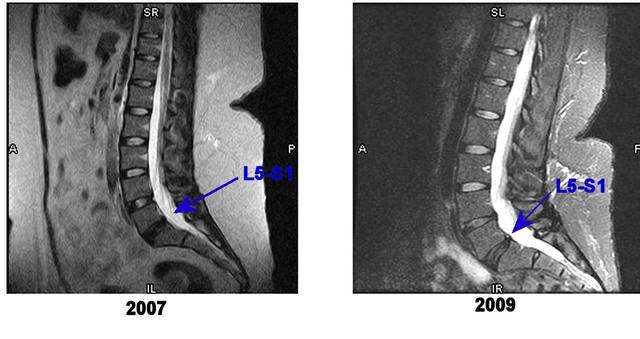

this is a comparison (though likely not "apples to apples" since i did it myself) of my 4/28/07 and 11/9/09 MRIs. only L5-S1 is labeled, but you can see that the L4-L5 disc is also degenerated by the fact that those are the 2 discs that lack color